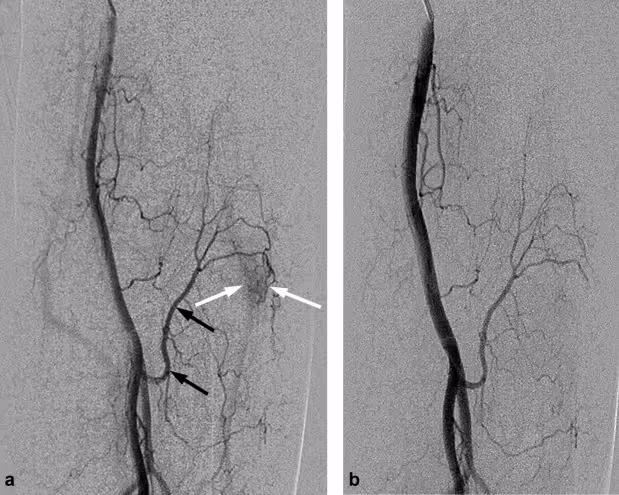

What Is Tennis Elbow Embolization?

Tennis Elbow Embolization (TEE) is a minimally invasive procedure performed by an interventional radiologist.

How it works:

Importantly:

The procedure usually takes under an hour and is done with local anesthesia.